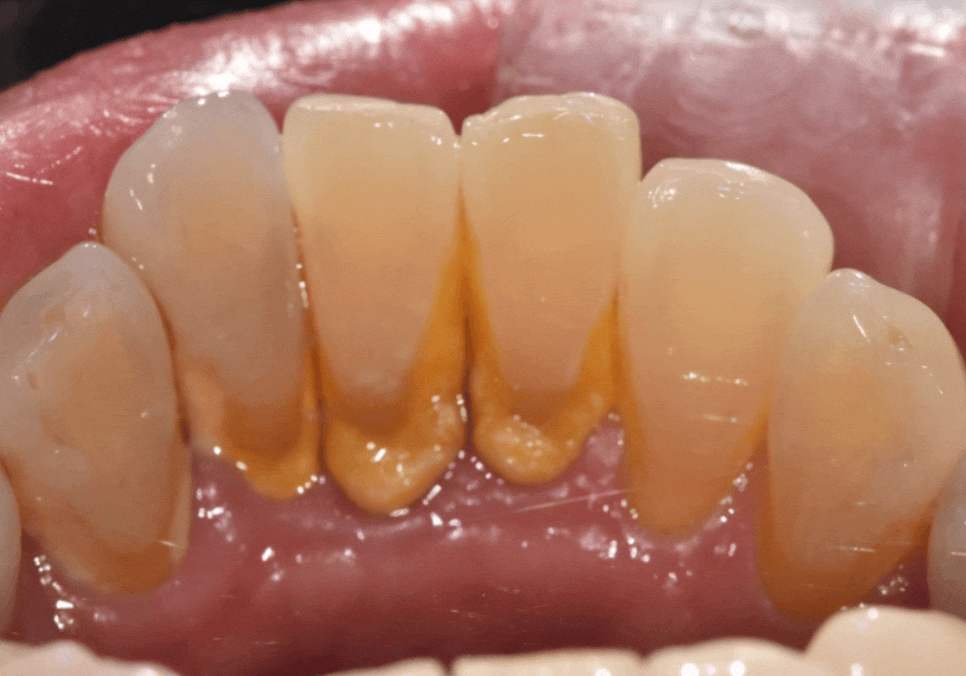

아래 앞니 안쪽은 우리 입안에서

치석이 유독 잘 쌓이는 부위입니다.

그 이유는 혀 밑에 위치한 '침샘' 때문인데요,

침 성분이 음식물 찌꺼기와 만나면

아주 빠르게 단단한 돌(치석)로 변하게 됩니다.

게다가 아래 앞니 안쪽은 구조상

칫솔질을 꼼꼼히 하기도 매우 어렵죠.

결국 스케일링을 차일피일 미루게 되면,

치석이 이불처럼 두꺼워지면서

잇몸에 심한 염증을 만듭니다.